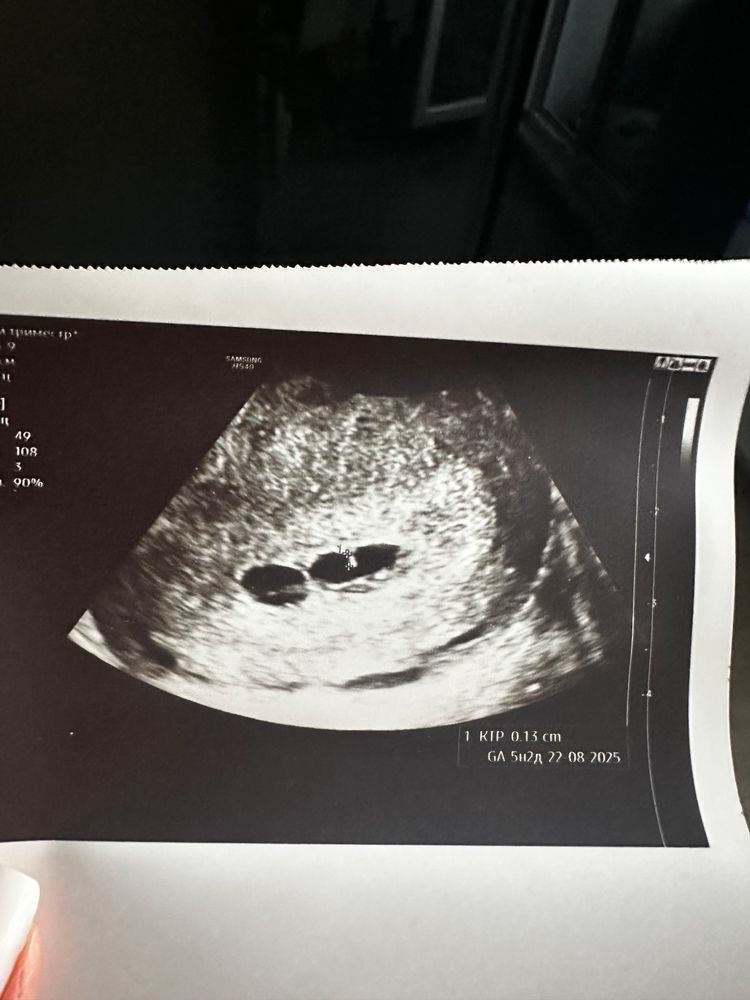

6 недель и 4 дня

Сходила на второе узи к другому узисту,тоже не понимает,что происходит,в заключении про плодное яйцо вообще ничего не пишет,говорит,что скорее всего не развивающаяся,потом говорит про возможность двойни😣ох уж эта неопределенность(Говорит,я могу предположить,что это начало развития эмбриона(на фото ниже),но это прямо совсем сомнительно,сказала😣

Она на всех снимках замерила ктр как бы))) значит, есть жм, есть уже даже эмбриончик, просто маленький совсем. На первом снимке не пойман жм, но четко виден эмбрион.